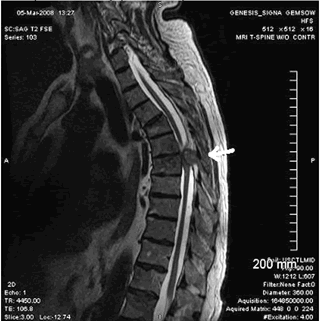

Оссификация желтой связки

Оссификация желтой связки - это линейное поражение связок дуги позвонка, характеризующееся линейной оссификацией в толще связки.

Наиболее частыми признаками являются хронические симптомы миелопатии грудного отдела позвоночника, проявляющиеся трудностями при передвижениях, слабостью мышц, болью в спине и парестезии в нижних конечностях. Изначально клиника поражения задних столбов спинного мозга, а вторичные проявления уже будут прогрессирующий спастический парапарез.

Магнитно-резонансная томография (МРТ)

- Т1-взвешенное изображение

- гипо- и гиперинтенсивные линейные зоны в толще желтой связки, которые могут компримировать спинной мозг

- гипоинтенсивные линейные зоны в толще желтой связки

- гипоинтенсивное утолщение желтой связки. На GRE изображениях возможна переоценка выраженности стеноза спинномозгового канала, что обусловлено наличием артефактов магнитной восприимчивости